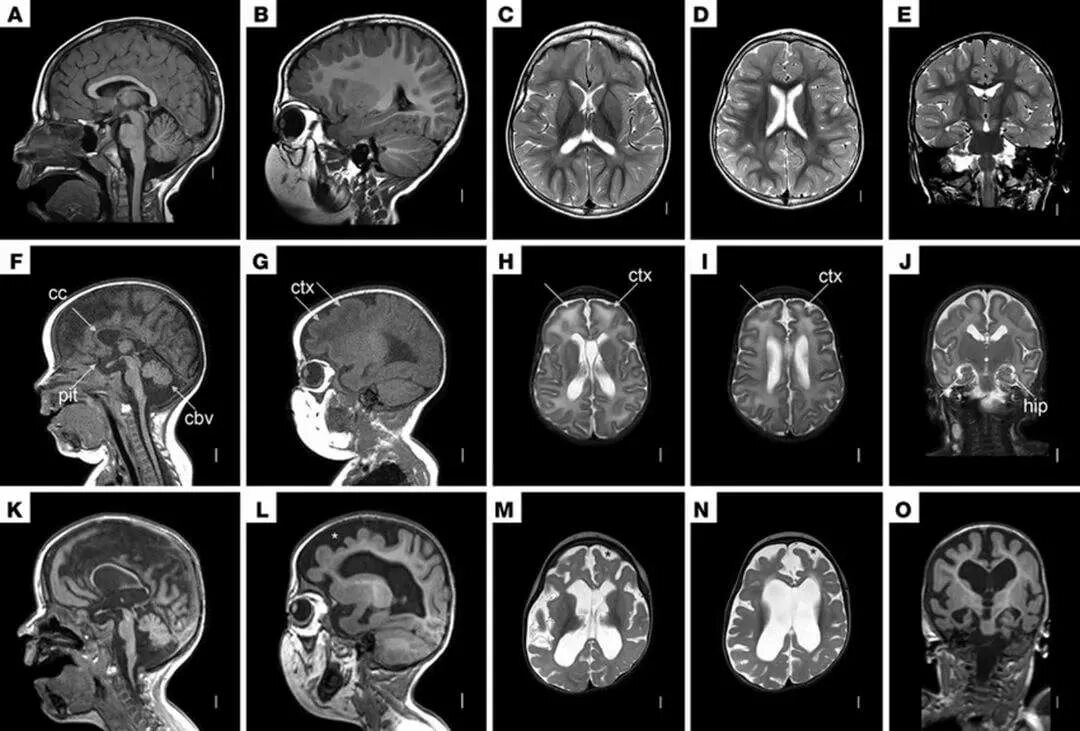

Кт пример